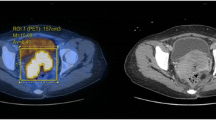

Statistical analysis

Representative axial fusion PET and T2-W images at various SUVmax cut-off percentages, and a T2-W image in the same patient. Volume of interest contours for the particular cut-off values are superimposed on the fusion images, and all volume of interest contours are superimposed on T2-W image for comparison

Representative axial PET and DW (ADC map) images at various SUVmax cut-off percentages in the same patient. Volume of interest contours for the particular cut-off values are superimposed on the ADC map. All volume of interest contours were finally superimposed on the PET image and ADC map for comparison